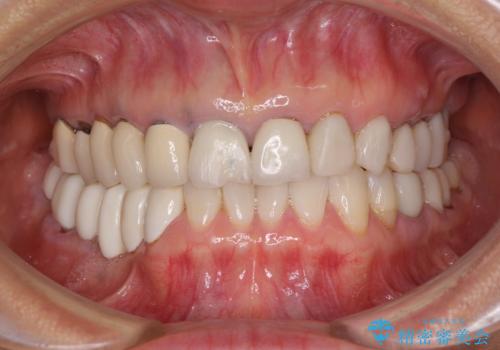

- 以前治療した歯が欠けたり、痛みを感じたりしているとのことで来院された患者様です。

アメリカ国内を転々としながら治療を行ったため治療跡がモザイク様で、クラウンが壊れていたり、抜歯が必要であったりしていました。

上下左右すべての奥歯に処置が必要であり、同時に行うと食事が取りにくくなってしまったり、手前の歯に負担がかかって初診時よりも状況が悪化したりする可能性があるため、片方ずつ処置を進めて行くこととしました。

下顎右側は骨造成を併用してインプラント治療を行い、その他の奥歯もインプラントや歯周外科処置を併用して補綴治療を進め、最後に前歯部の欠けてしまったセラミッククラウンを作り替えることとしました。